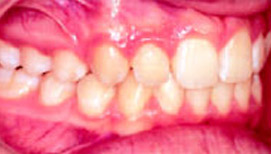

Эластопозиционеры эффективны и для коррекции окклюзии после предшествующего лечения другими методами: одночелюстными или двухчелюстными аппаратами или Quad-Helix. При расширении зубных рядов или сагиттальном перемещении нижней челюсти появляется вертикальная щель в области премоляров, а при устранении дистопии клыков – в области клыков. Созданный на Set-up желаемый вид окклюзии достигается в течение всего нескольких недель (рис.7-9).

Рис.7: Аномалия II класса, проведено предварительное лечение двухчелюстным аппаратом.

Рис.8: Set-up для достижения точной окклюзии.

Рис.9: Через 3 месяца после начала ношения аппарата.